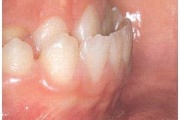

kaaries igemeäärel

kaaries